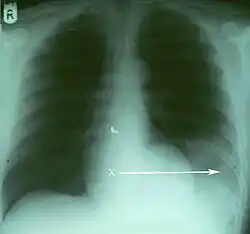

Verletzungen der Lunge können neben einer Lungenkontusion als Quetschverletzung Lungenrisse sein. Letztere führen zu einem Pneumothorax, wie er bei 10 bis 50 Prozent der Patienten mit Thoraxtrauma auftritt,[6] und gegebenenfalls zu einem Spannungspneumothorax. Blutungen in den Thorax hinein führen zu einem Hämatothorax. Bei einem Hämatopneumothorax treten sowohl ein Pneumo- als auch ein Hämatothorax in Kombination auf. Symptome sind zunächst Luftnot und je nach Ausmaß der Blutung auch Kreislaufinstabilität. Bei einem Pneumothorax kann sich insbesondere bei Ausbildung eines Spannungspneumothorax ein Hautemphysem bilden, das eine große Ausdehnung erreichen kann. Therapie ist eine Entlastung der Pleurahöhle mittels Thoraxdrainage auf der betroffenen Seite. Üblicherweise kommen kleinere intrathorakale Blutungen von alleine zum Stehen, so dass außer einer Drainage keine weiteren Maßnahmen notwendig werden. Eine Thorakotomie zur operativen Blutstillung kann bei einem initialen Blutverlust von mehr als 1.500 ml nach der Thoraxdrainage oder bei einem fortwährenden Blutverlust von mehr als 250 ml pro Stunde über mehr als vier Stunden erfolgen.[2][5]

Thorako-abdominelle Verletzungen

Die Kombinationsverletzung von Thorax und Abdomen ist die vierthäufigste Kombination bei mehrfachverletzten Patienten.[2] Insbesondere Zwerchfell, Leber und Milz sind auch bei isolierten Thoraxtraumen oft mitbetroffen. So können beim stumpfen Thoraxtrauma gebrochene Rippen in Leber oder Milz spießen und starke Blutungen verursachen. Durch ein plötzliches Kompressionsereignis kann das Zwerchfell ein- oder beidseits rupturieren und es kann zur Verlagerung von Bauchorganen in den Brustkorb kommen. Hierbei kommt es zu einer mechanischen Kompression der Lungen mit Luftnot und abgeschwächtem Atemgeräusch auf der betroffenen Seite. Bei einer rechtsseitigen Zwerchfellruptur liegt mit sehr großer Wahrscheinlichkeit auch eine schwere Verletzung der Leber vor.[2] Bei penetrierenden Thoraxtraumen können die in den Körper eindringenden Fremdkörper wie Projektile oder Messer sich bis in den Bauchraum bewegen und dortige Organe mitverletzen.[2] Symptome von intraabdominellen Organverletzungen sind Schock und Anzeichen eines akuten Abdomens.[2]